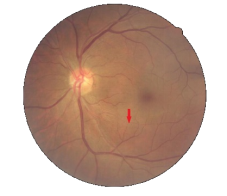

编者按:脑卒中是威胁人类健康的重要疾患,早期识别危险人群、实现关口前移是脑卒中防治亟待解决的重大命题。视网膜神经纤维层是中枢神经系统的一部分,是活体唯一可以直接观察到的神经组织。简单的眼底照相可作为观测慢性疾病,特别是心脑血管疾病的良好窗口。以往的研究表明,既往脑卒中史或急性脑卒中均与视网膜神经纤维层缺损密切相关。然而目前没有研究将视网膜神经纤维层缺损作为生物标志物,探索其对脑卒中的风险预测价值。通过眼底影像预测全身系统疾病的发生、发展和转归一直是国际研究的焦点,具有重要的临床意义。首都医科大学附属同仁医院杜葵芳博士、王亚星教授及魏文斌教授团队通过前瞻性队列研究,探讨了视网膜神经纤维层缺损对5年内发生脑卒中的预测价值进行了分析。

研究发现,在5年的随访中(平均46±9个月),脑卒中事件平均发生在入组后的第22个月(95%置信区间:20 - 24个月)。将发生脑卒中事件患者与随机筛选的年龄和性别匹配的对照组进行比较,发现脑卒中事件患者的视网膜神经纤维层缺损基线患病率明显高于对照组(分别为43.3%±3.4%和9.8%±0.6%);优势比(OR):7.05;P < 0.001)。

Cox比例风险模型显示,在校正年龄、性别和糖尿病或高血压病后,视网膜神经纤维层缺损患者的脑卒中发生风险显著增加(P<0.001),风险比(HR)为5.75 (95% CI: 4.13- 8.02)。

视网膜神经纤维层是一种无髓鞘的中枢神经系统轴突。非青光眼相关的视网膜神经纤维层缺损被认为是局部血管功能不全导致的神经节细胞丢失。相似的病理学改变提示视网膜神经纤维层缺损和脑血管事件之间有很强的相关性。当眼底出现神经纤维层缺损时,可提示有出现脑血管事件(脑卒中)的风险。

该项研究全球首次证实了视网膜神经纤维层缺损对脑卒中具有预测价值,可作为预测未来脑卒中风险增加的生物标志物之一。研究结果对脑卒中防治策略的有重要的参考意义。